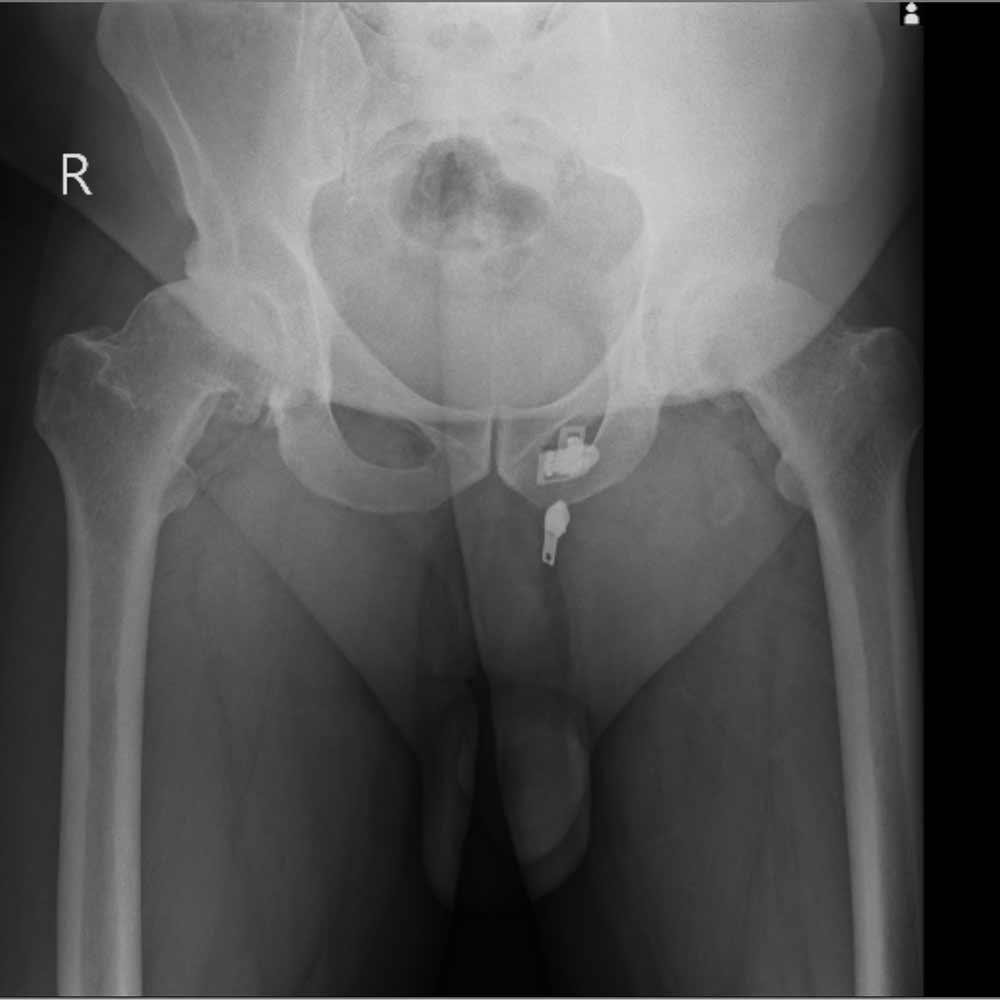

در نهایت، روش های تصویر برداری مثل رادیوگرافی به تشخیص بیماری کمک میکند. مهمترین روش تصویربرداری برای تشخیص ساییدگی لگن رادیوگرافی ساده است. تشخیص این بیماری نیاز به سی تی اسکن یا ام ار آی ندارد.

در تصویر رادیوگرافی از مفصل، چون غضروف نازک شده است فاصله مفصلی یا فاصله بین دو استخوانی که مفصل را تشکیل داده اند و در حد چند میلیمتر است کاهش پیدا میکند و در کناره های استخوان های تشکیل دهنده مفصل استخوان اضافی دیده میشود.

همچنین ممکن است کیست های استخوانی در بالای استابولوم یا در سر استخوان ران دیده شود.

در زیر تصاویری از عکس ساییدگی لگن در چند بیمار را میبینید. با کلیک بر روی هر کدام تصویر بزرگتری از آن را خواهید دید.